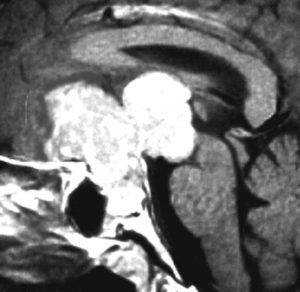

巨大な前頭底部ジャーミノーマ

少年のものです。数年の経過のゆっくりした認知機能低下で発症しました。学業が不振でしたが気づかれず増大したものです。初診時には,認知機能障害,尿崩症,汎下垂体機能低下症,高度の両側視力低下でした。こんなものでもICE化学療法1コースでほとんど消失します(右側の画像は2コース後かつ放射線治療前のMRI)。ですから,無理して開頭摘出術をしない。